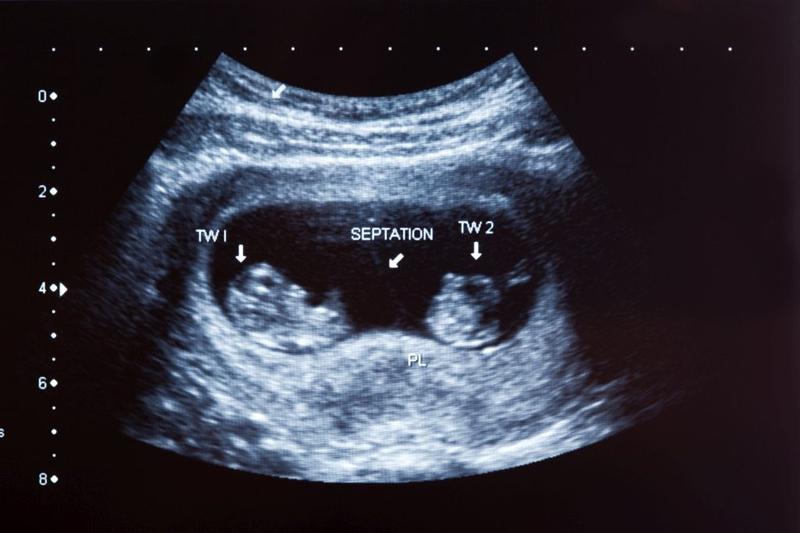

Temat ciąż bliźniaczych od zawsze fascynuje nie tylko przyszłych rodziców, lecz także miłośników różnorodnych ciekawostek. W końcu kto nie chciałby marzyć o podwójnym szczęściu? Choć statystycznie ciąża bliźniacza występuje tylko w jednym na 80 porodów, w ostatnich latach zauważamy znaczący wzrost takich przypadków. Dlaczego tak się dzieje? Z pewnością czynniki genetyczne odgrywają tutaj kluczową rolę. Obecność bliźniaków w rodzinie zwiększa szansę na ich narodziny! Niemniej jednak, nie tylko geny mają znaczenie – istnieją także inne aspekty, które mogą sprawić, że wkrótce w twoim życiu pojawią się dwojaczki.